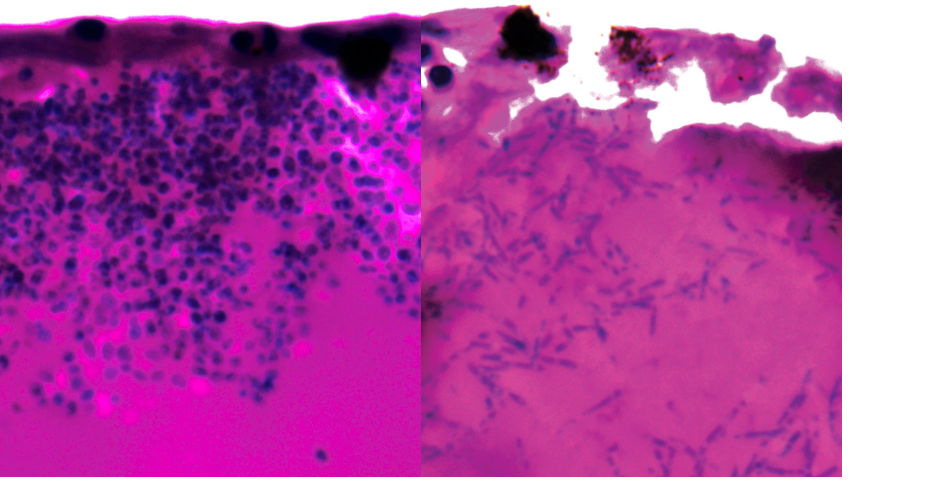

Candida auris during infection. Right hand image shows filaments

The researchers discovered that Candida auris can switch to form elongated bodies of fungus, known as filaments, possibly to search for nutrients.